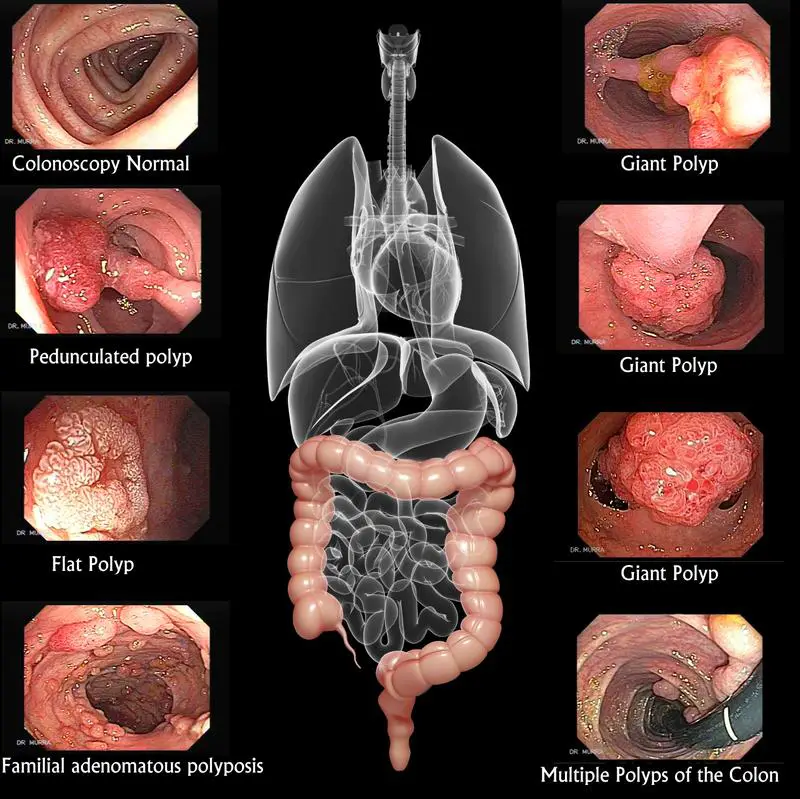

One of these viewing tests is sigmoidoscopy, which takes 10-20 minutes, during which the doctor uses a thin, flexible tube with a light to look inside the rectum and lower intestine or colon. With this procedure, the physician can see if there is any bleeding, inflammation, abnormal growths, or ulcers. Sigmoidoscopy enables the doctor to see the bottom one-third of the colon. Another procedure, colonoscopy, enables the doctor to see the entire colon. For this test, which also involves the use of a lighted tool, a patient is mildly sedated to keep her or him relaxed and comfortable.

During colonoscopy as well as sigmoidoscopy, should the doctor see benign growths known as polyps (that could later become malignant) he or she can do a biopsy (take a sample of the tissue) and/or remove the polyp on the spot. Patients are not allowed to drive home after a colonoscopy because of lingering drowsiness, so another driver must accompany them to the visit.